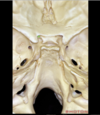

Arcuate eminence

Meatal depression

Petrous temporal bone

Sigmoid sinus

Superior petrosal sinus

Tegmen

What bones form the foramen lacerum?

Foramen lacerum formed by the junction of the petrous apex, sphenoid bone and occipital bone

What bounds the lateral edge of the carotid groove of the sphenoid bone?

The lingula

Optic canal

Planum sphenoidale which forms the roof of the sphenoid sinus

Dorsum sella which forms the upper clivus

This is the petroclival fissure in which the inferior petrosal sinus runs